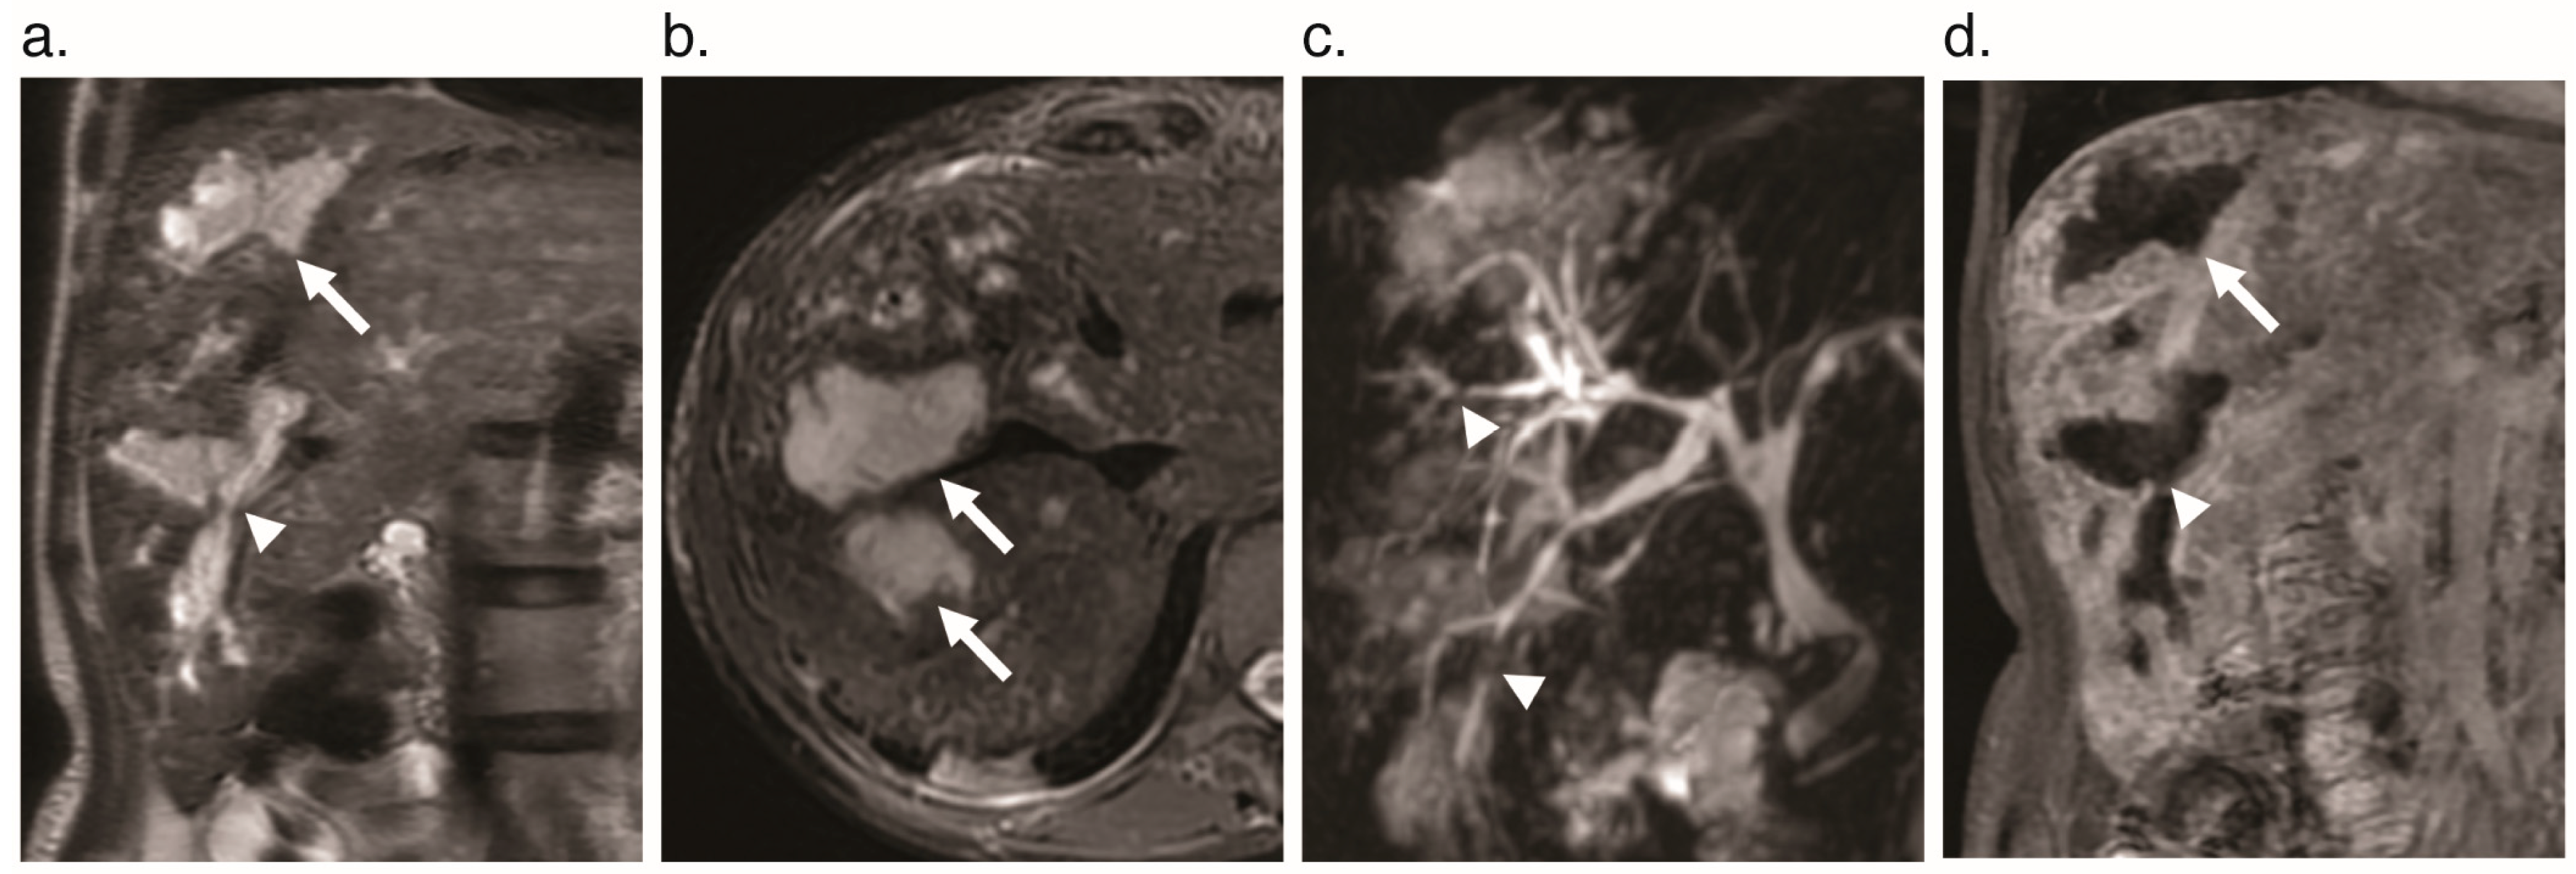

6.3. Cholangiopathy

- Scardapane, A.; Ficco, M.; Sabba, C.; Lorusso, F.; Moschetta, M.; Maggialetti, N.; Suppressa, P.; Angelelli, G.; Ianora, A.A.S. Hepatic nodular regenerative lesions in patients with hereditary haemorrhagic telangiectasia: Computed tomography and magnetic resonance findings. La Radiol. Med. 2012, 118, 1–13. [Google Scholar] [CrossRef]